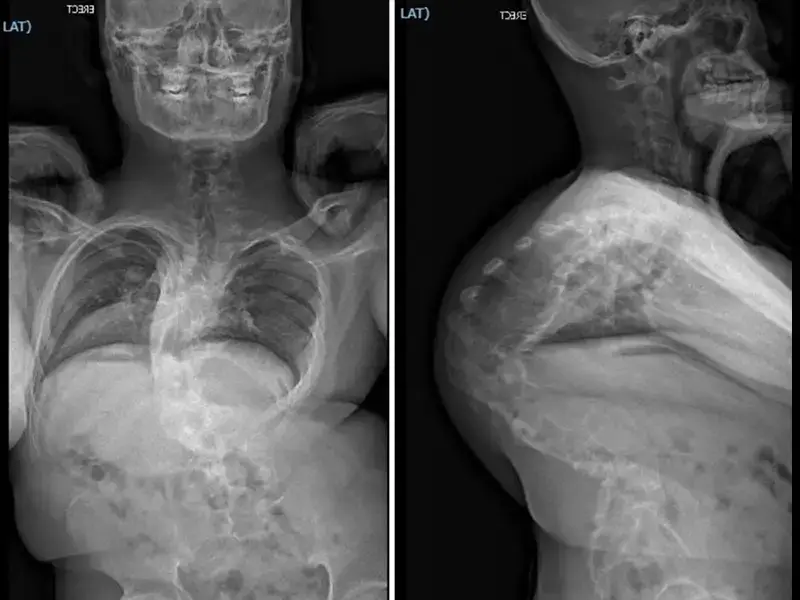

Extensive Multistage Spine Surgery Transforms A Severe Case Of Kyphoscoliosis

An adolescent patient born with congenital kyphoscoliosis, which progressed to 140 degrees kyphosis and 56 degrees scoliosis, traveled from the Philippines to New York for surgical treatment led by Lawrence Lenke, M.D., co-director of Och Spine at NewYork-Presbyterian and chief of spinal deformity surgery at NewYork-Presbyterian and Columbia. Dr. Lenke developed a treatment plan consisting of several staged procedures over six weeks, including halo gravity traction, rib resection, installation of an interbody cage, placement of rods and screws, removal of several vertebrae, placement of bone material, and irrigation and debridement to promote optimal wound healing. The surgeries successfully corrected the curvatures and fused the spine into proper position, with the patient expected to return to normal life without limitations.